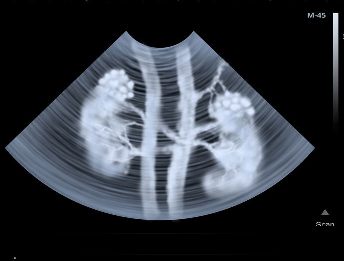

A Renal DTPA (Diethylenetriamine Pentaacetic Acid) Scan is a nuclear medicine test to assess kidney function, blood flow, and drainage. It involves injecting a small amount of a radioactive tracer, which a gamma camera detects. This scan can detect a blockage in one of the arteries leading to the kidneys, which might cause your raised blood pressure. It can also tell how well each of your kidneys is working.

The Renal DTPA scan provides dynamic imaging of the kidneys, allowing doctors to monitor renal perfusion (blood supply), glomerular filtration, and excretion. It differs from a Renal MAG3 scan, often preferred for patients with poor kidney function.